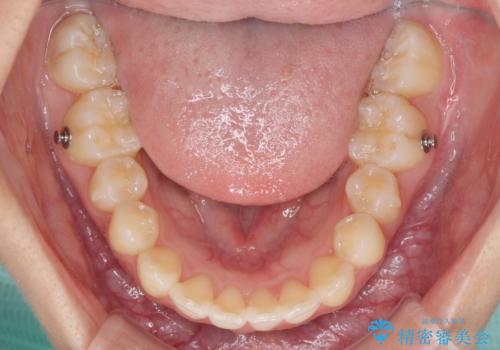

インビザラインによる上下歯列の側方拡大と後方移動、IPR(歯と歯の間を削る)にるスペースの獲得により歯列を整えることとしました。

骨格的な左右差があったため、上下の正中を合わせることは困難かと思われましたが、何とか合わせることができました。

一方、骨格の差は改善できないため、奥歯の咬み合わせに物足りなさを感じました。

奥歯の咬み合わせによる不自由はなく、患者様に大変満足していただきました。